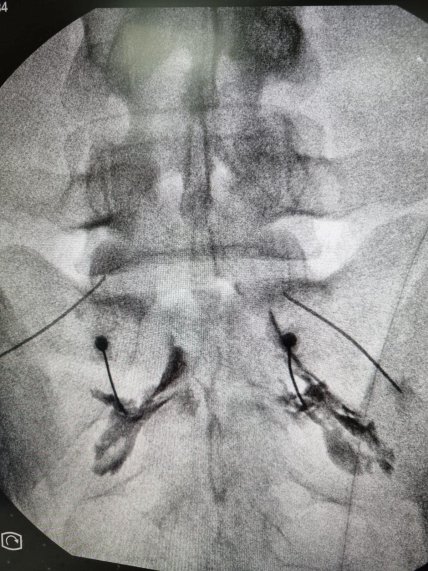

Юрій Кормишкін рентген